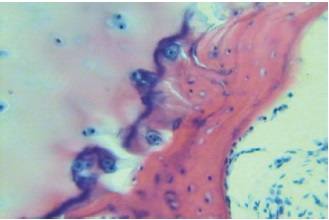

After premedication in a clean operating room under spinal anesthesia, in the position of the patient on his back with a roller under the affected leg, anterior approach to the ankle joint was performed, followed by capsulotomy of the ankle joint. The clinical probe demonstrated the instability of distal tibiofibular syndesmosis, which was an indication for the removal of interpolating tissues, reduction of the fibula into a tibiofibular notch and fixation with a syndesmotic bolt. Reconstruction of the stretched anterior tibiofibular and anterior talofibular ligaments with local tissues was performed. Intraoperatively, bone ankylosis was noted in the subtalar joint. The affected talus was completely removed by fragmentation. The remains of the articular gap of the subtalar joint filled with fragments of articular cartilage, bone and connective tissue served as a guideline for the removal of the talus. Pathologically altered tissues together with hypertrophied synovial membrane were sent for histological examination, which showed irreversible degenerative changes in articular surfaces (Fig. 5). The attempt to implant the total talus endoprosthetics failed due to the gross deformation of the tibial pylon.

Fig. 5. The necrosis of the talus block: destruction of the basophilic line, introduction of the necrosis process into cartilage tissue. Stained with hematoxylin and eosin. Mag. ×200